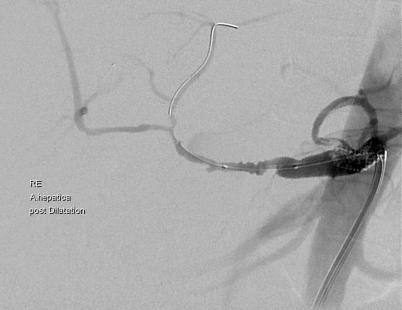

Abb. 5

Angiographie bei liegendem Angiographiekatheter und Status nach Dilatation am Abgang des Truncus coeliacus bei Dunbar-Syndrom. Die A. hepatica mit postinterventionellen reaktiven Spasmen. (Die Aufnahme wurde dankenswerterweise von Hr. Univ. Prof. H. Portugaller, Universitätsklinik für Radiologie Graz zu Verfügung gestellt)

Ischämische Komplikationen

Ischämien sind mit knapp 2 % zwar selten, können aber zu schwer beherrschbaren und lebensbedrohlichen Situationen führen [36, 37]. Meist sind Dissektionstraumen an den Gefäßen und Stenosen am Truncus coeliacus dafür verantwortlich. Kreuzt das Ligamentum arcuatum auf Höhe des Truncus coeliacus, kann dies zu einer extraluminalen Kompression am Abgang des Truncus und dadurch zu einer konsekutiven Ischämie führen (Dunbar- oder Ligamentum-arcuatum-Syndrom) (Abb. 5). Nur etwa 1 % der Menschen, leiden an einem derartigen Kompressionssyndrom [38].

Somit bekommt die Computertomographie nicht nur einen tumorassoziierten Stellenwert bezogen auf das Staging, sondern hat auch die Erfordernisse für eine Erhebung des versorgungsrelevanten Gefäßstatus zu erfüllen. Bei Vorliegen signifikanter Stenosen, ist präoperativ eine radiologische Intervention angezeigt, die entweder in Form einer PTA oder mittels Applikation von Stents erfolgen kann. Bei einer Abgangsstenose am Truncus coeliacus muss intraoperativ bedingt durch das Ligamentum arcuatum die Spaltung des Ligaments erfolgen.